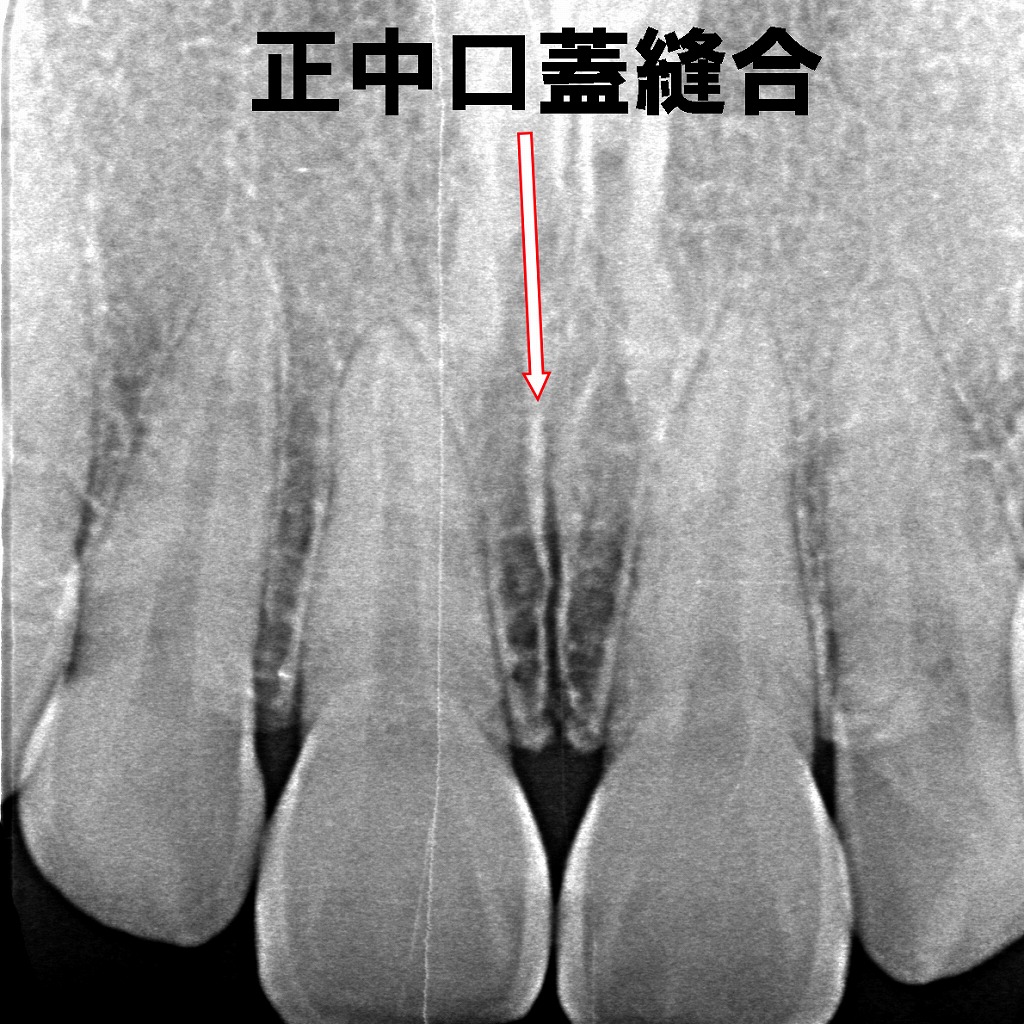

🦷 正中口蓋縫合とは

上顎骨は、胎児期に左右2つの骨が癒合して形成されます。その接合線が「正中口蓋縫合」であり、成人になってもわずかに認められることがあります。

装置の中心にあるネジを毎日少しずつ回すことで、上顎の中央にある「正中口蓋縫合(せいちゅうこうがいほうごう)」を開き、骨を拡大していきます。これにより歯が並ぶスペースを確保したり、鼻腔を広げて呼吸を助けたりすることが可能になります。